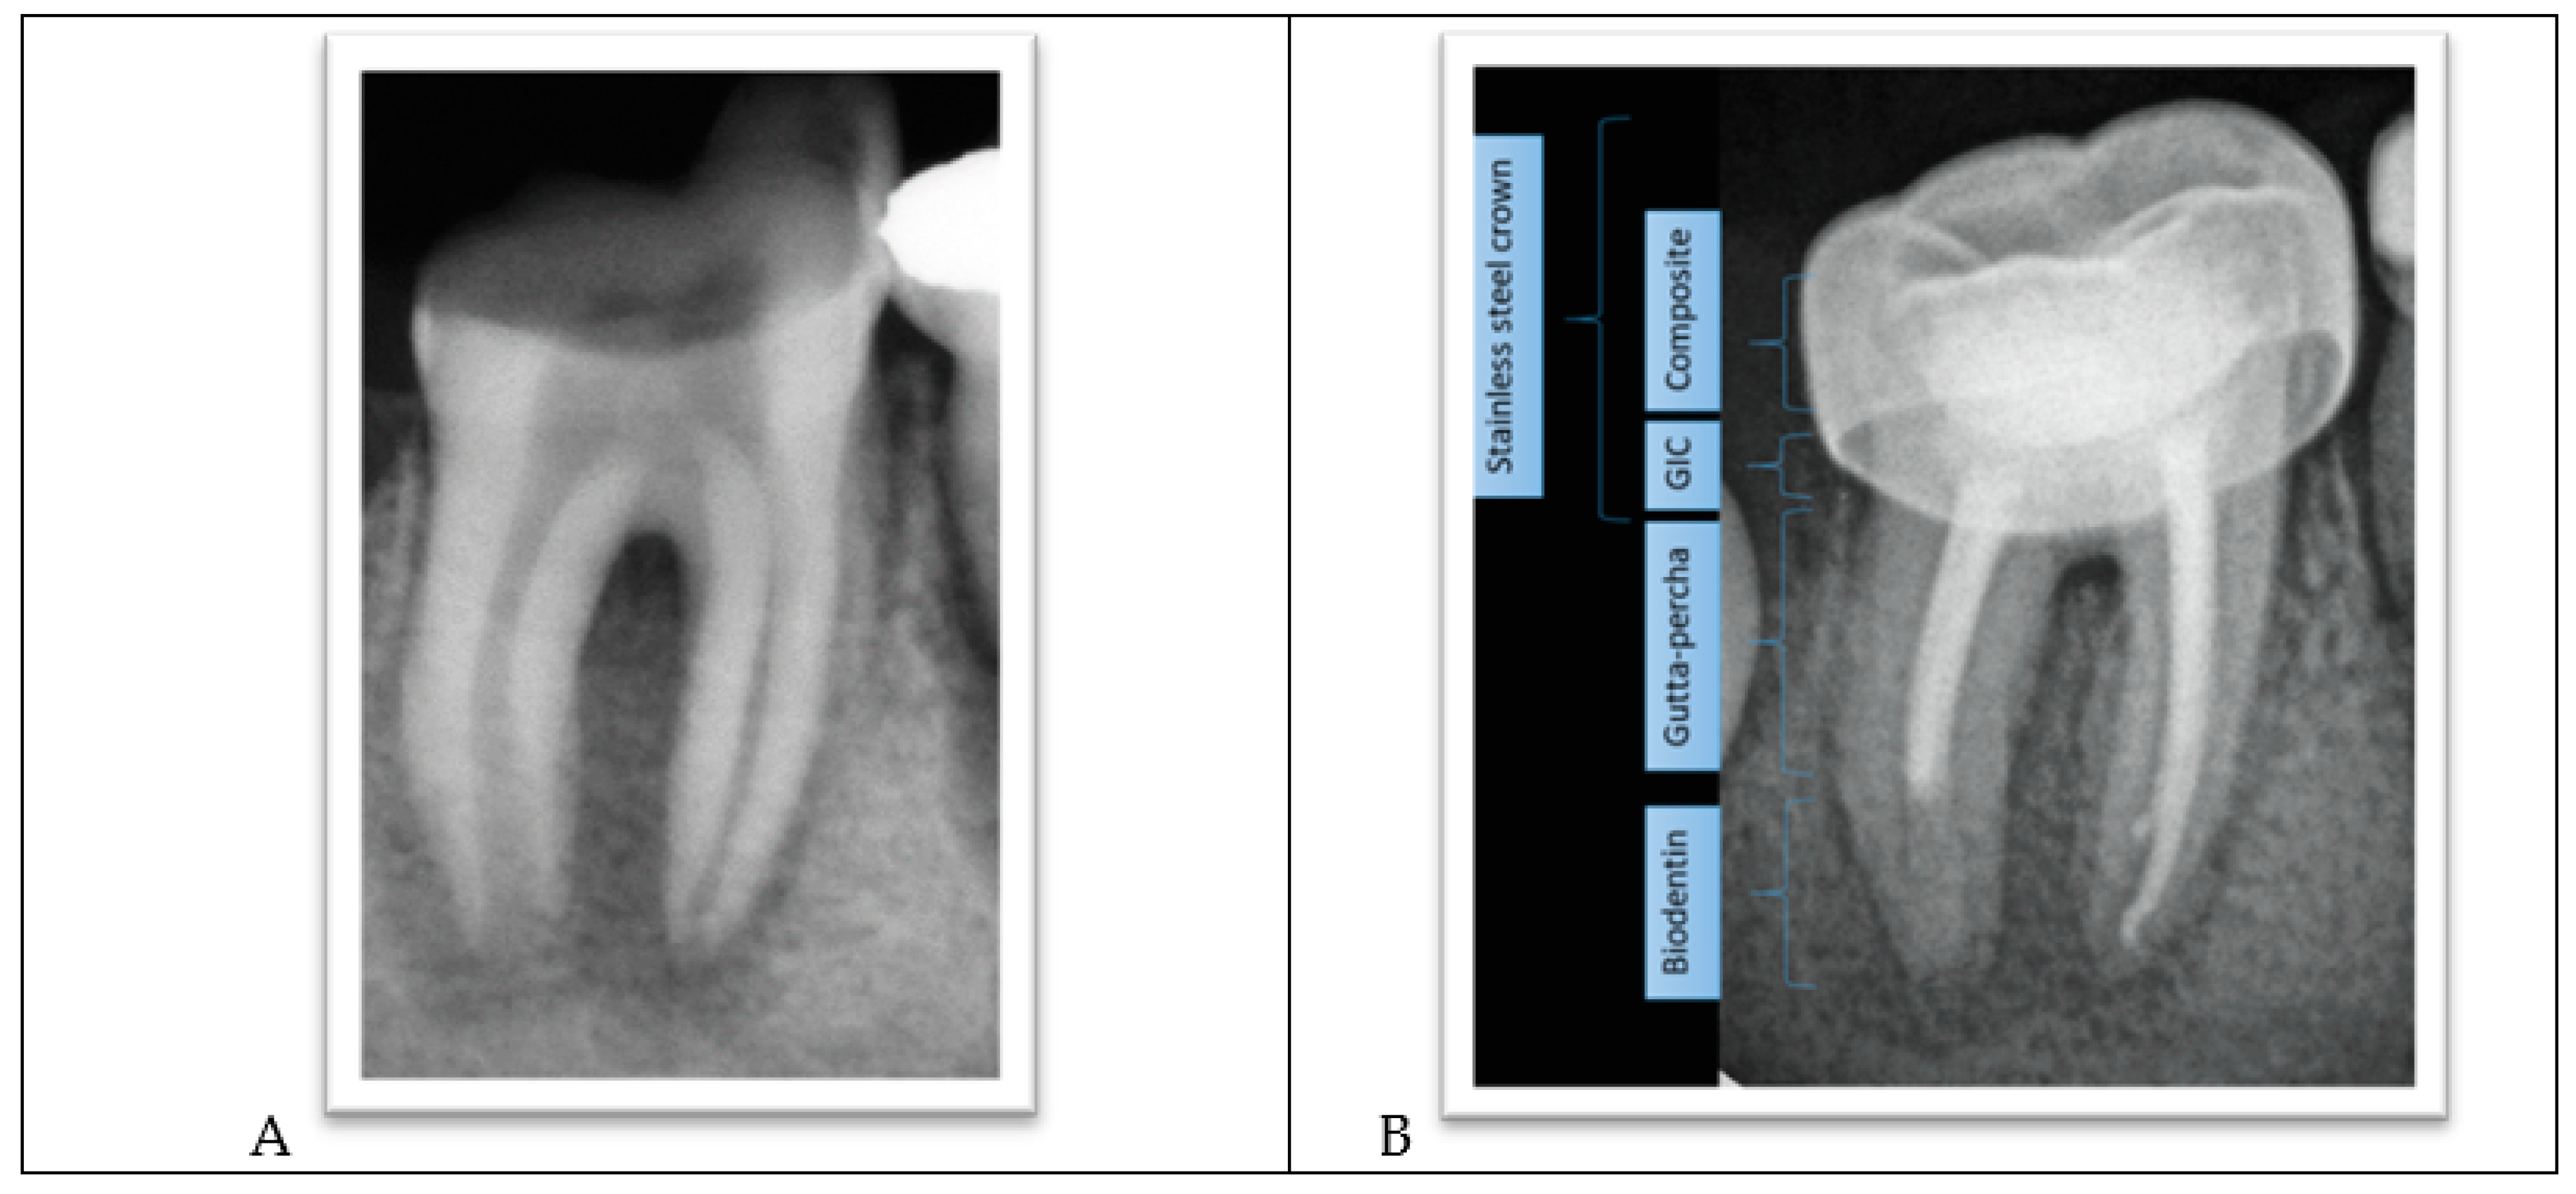

The lower-right permanent molar (tooth #46) was treated similarly to tooth #36, but Biodentine (Septodont) was used as an apical plug in one session instead of MTA to reduce treatment sessions. The root canal’s remainder was filled with gutta-percha, and the tooth was restored, similar to tooth #36 (Figure 5A,B).

Figure 5.

(A) Apical lesions with extensive decay in tooth #46. (B) Biodentine placement, completed root canal treatment, and placement of a metallic crown.